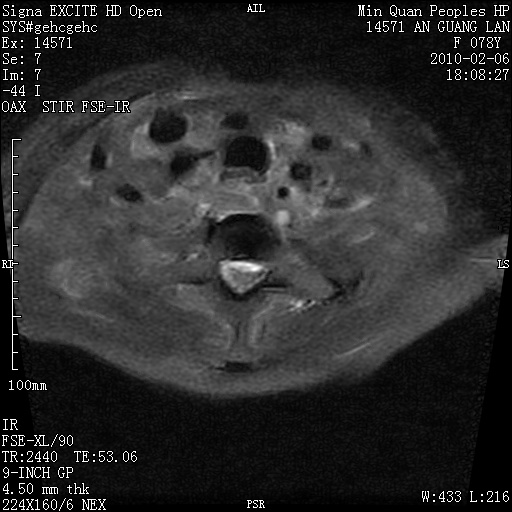

标题: MRI2763:C6、C7椎体病变性质?

f,78y,颈部与双上肢阵发性剧痛40余天。ct可见c6、c7椎体虫蚀样破坏,其间椎间隙变窄(没有图片资料可供上传)。

考虑椎体结核并椎旁脓肿。

支持 c6、7椎体结核并椎旁冷脓肿形成。

考虑:c6/7椎体结核并椎旁脓肿形成,建议增强扫描。